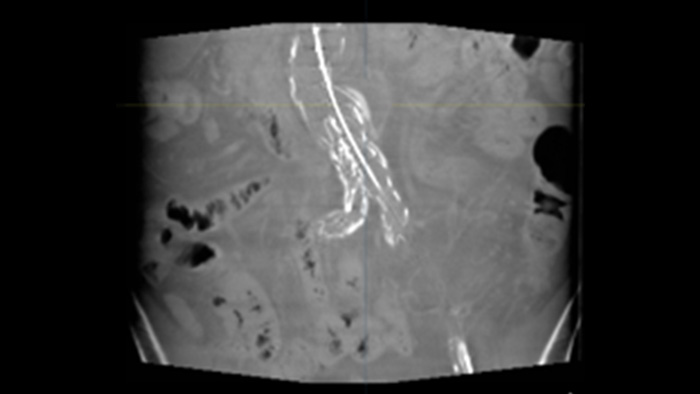

L'échographie intravasculaire (IVUS) est une technologie d'imagerie par cathéter qui permet aux médecins de visualiser les vaisseaux sanguins de l'intérieur vers l'extérieur pour faciliter l'évaluation de la présence et de l'étendue de la maladie. L'IVUS aide à décider, guider et confirmer le traitement interventionnel approprié pour chaque patient.

IntraSight fournit plus d'informations grâce aux modalités iFR/FFR et IVUS en conjonction avec le contrôle de l'écran tactile côté table de l'angiogramme. Il est construit sur une plate-forme de base capable d'ajouter rapidement de nouvelles innovations à votre laboratoire.